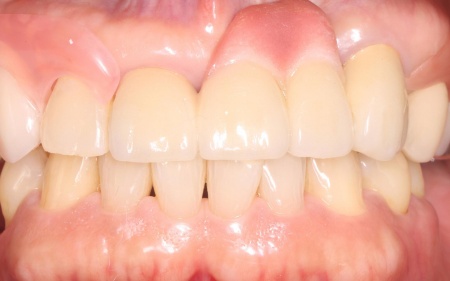

治療前

治療中

治療後

| 診断 | 拝見したところ、インプラントの手前の歯には保険の金属製の被せ物(銀歯)が装着されていました。 しかし、被せ物と歯の間にわずかな隙間や段差が生じており、ぴったりと合っていない状態でした。 このような隙間には、食べかすなどの汚れや虫歯や歯周病の原因となる細菌の塊「プラーク」が蓄積しやすくなります。 レントゲンを撮り確認したところ、現時点では歯の神経や根の状態に異常は認められなかったものの、このまま放置すると、被せ物の隙間からプラークの蓄積が進み虫歯や歯周病になる恐れがあります。 以上のことから、患者様のご希望も踏まえ被せ物のやり直しが必要と診断しました。 |

| 行ったご提案・治療内容 | 患者様は「強度があって見た目もいいものがいい」と希望されており、被せ物にはセラミック素材の一種であるオールジルコニアクラウンを提案し、同意いただきました。

ジルコニアは天然歯に近い白さと自然な質感を再現できるうえ、強度が高いため奥歯のように噛む力がかかる部位にも適した素材です。 まず、既存の銀歯を丁寧に除去します。 なお、治療後に患者様より「もう1本手前の銀歯もやり直したい」とのご希望があり、後日こちらも被せ物をやり直す予定です。 |